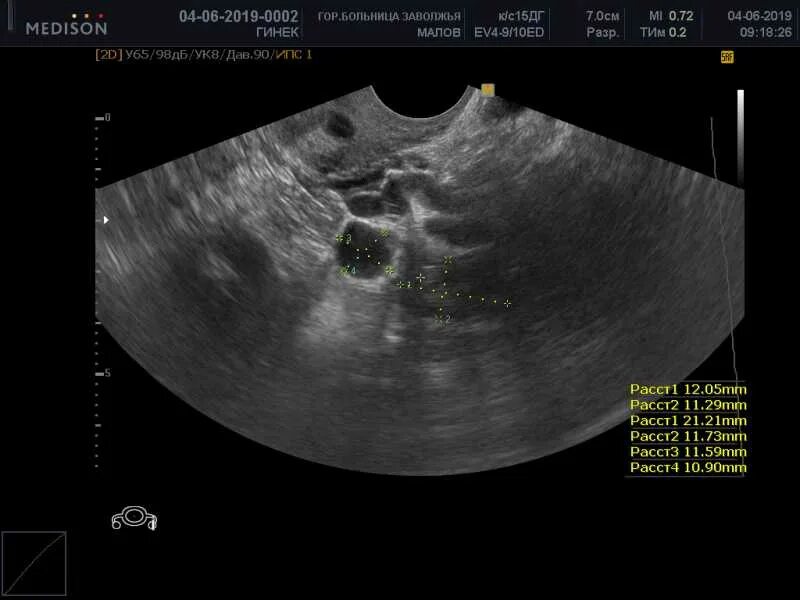

Киста уменьшается в размере